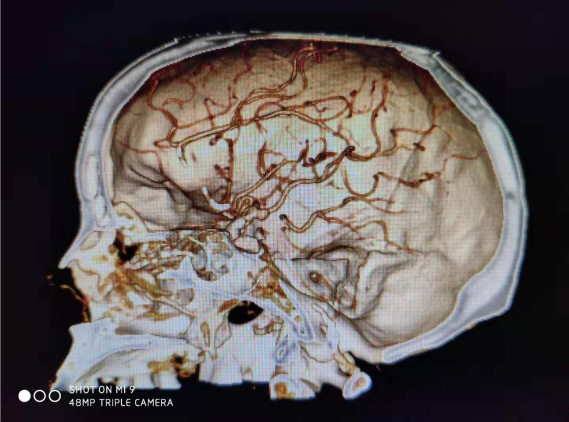

病例一:患者女性,49岁,因突发意识不清2小时,伴喷射性呕吐,大汗、四肢抽搐,就诊于本院神经外科接受治疗。积极完善相关检查,患者处浅昏迷,格拉斯评分7分,CT示:左侧额颞叶脑出血,量约33ml,并急诊行CTA(血管造影)示:左侧大脑中动脉M2段动脉瘤。急诊行“颅内血肿清除术+颅内动脉瘤夹闭+去骨瓣减压”,手术顺利,目前患者治愈出院。